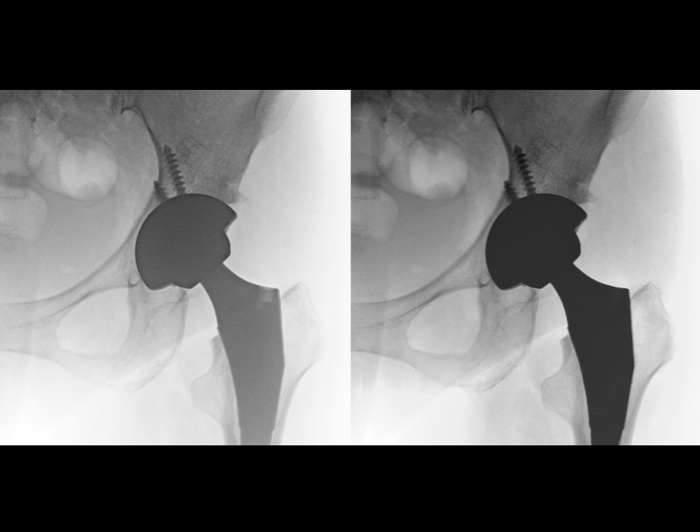

200万像素带来2倍于常规的信息采集量,大幅度减少信号损失,清晰捕捉微小解剖结构,提升诊断准确性。

空间分辨率高达3.3lp/mm,多级视野放大,图像细节仍清晰可见。